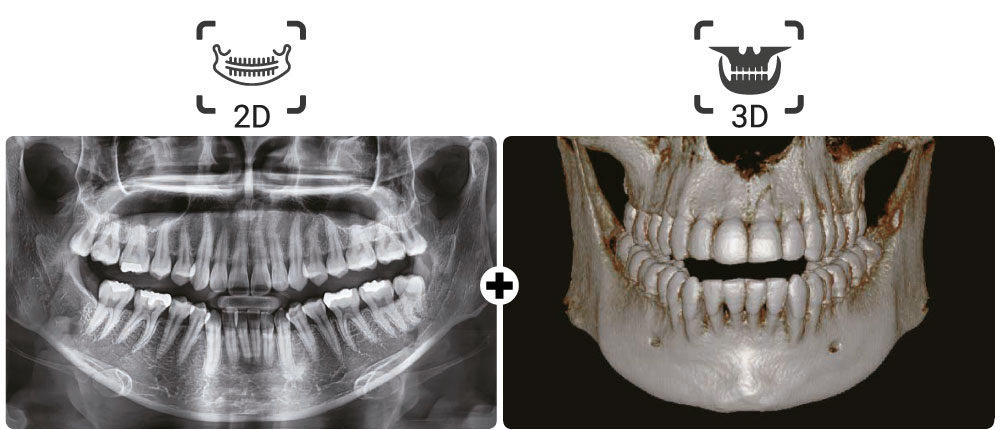

3D и 2D в одной программе

Одновременный просмотр 2D и 3D-изображений в одной программе помогает пациентам лучше понять о чем говорит доктор, что способствует более быстрому и простому принятию плана лечения.